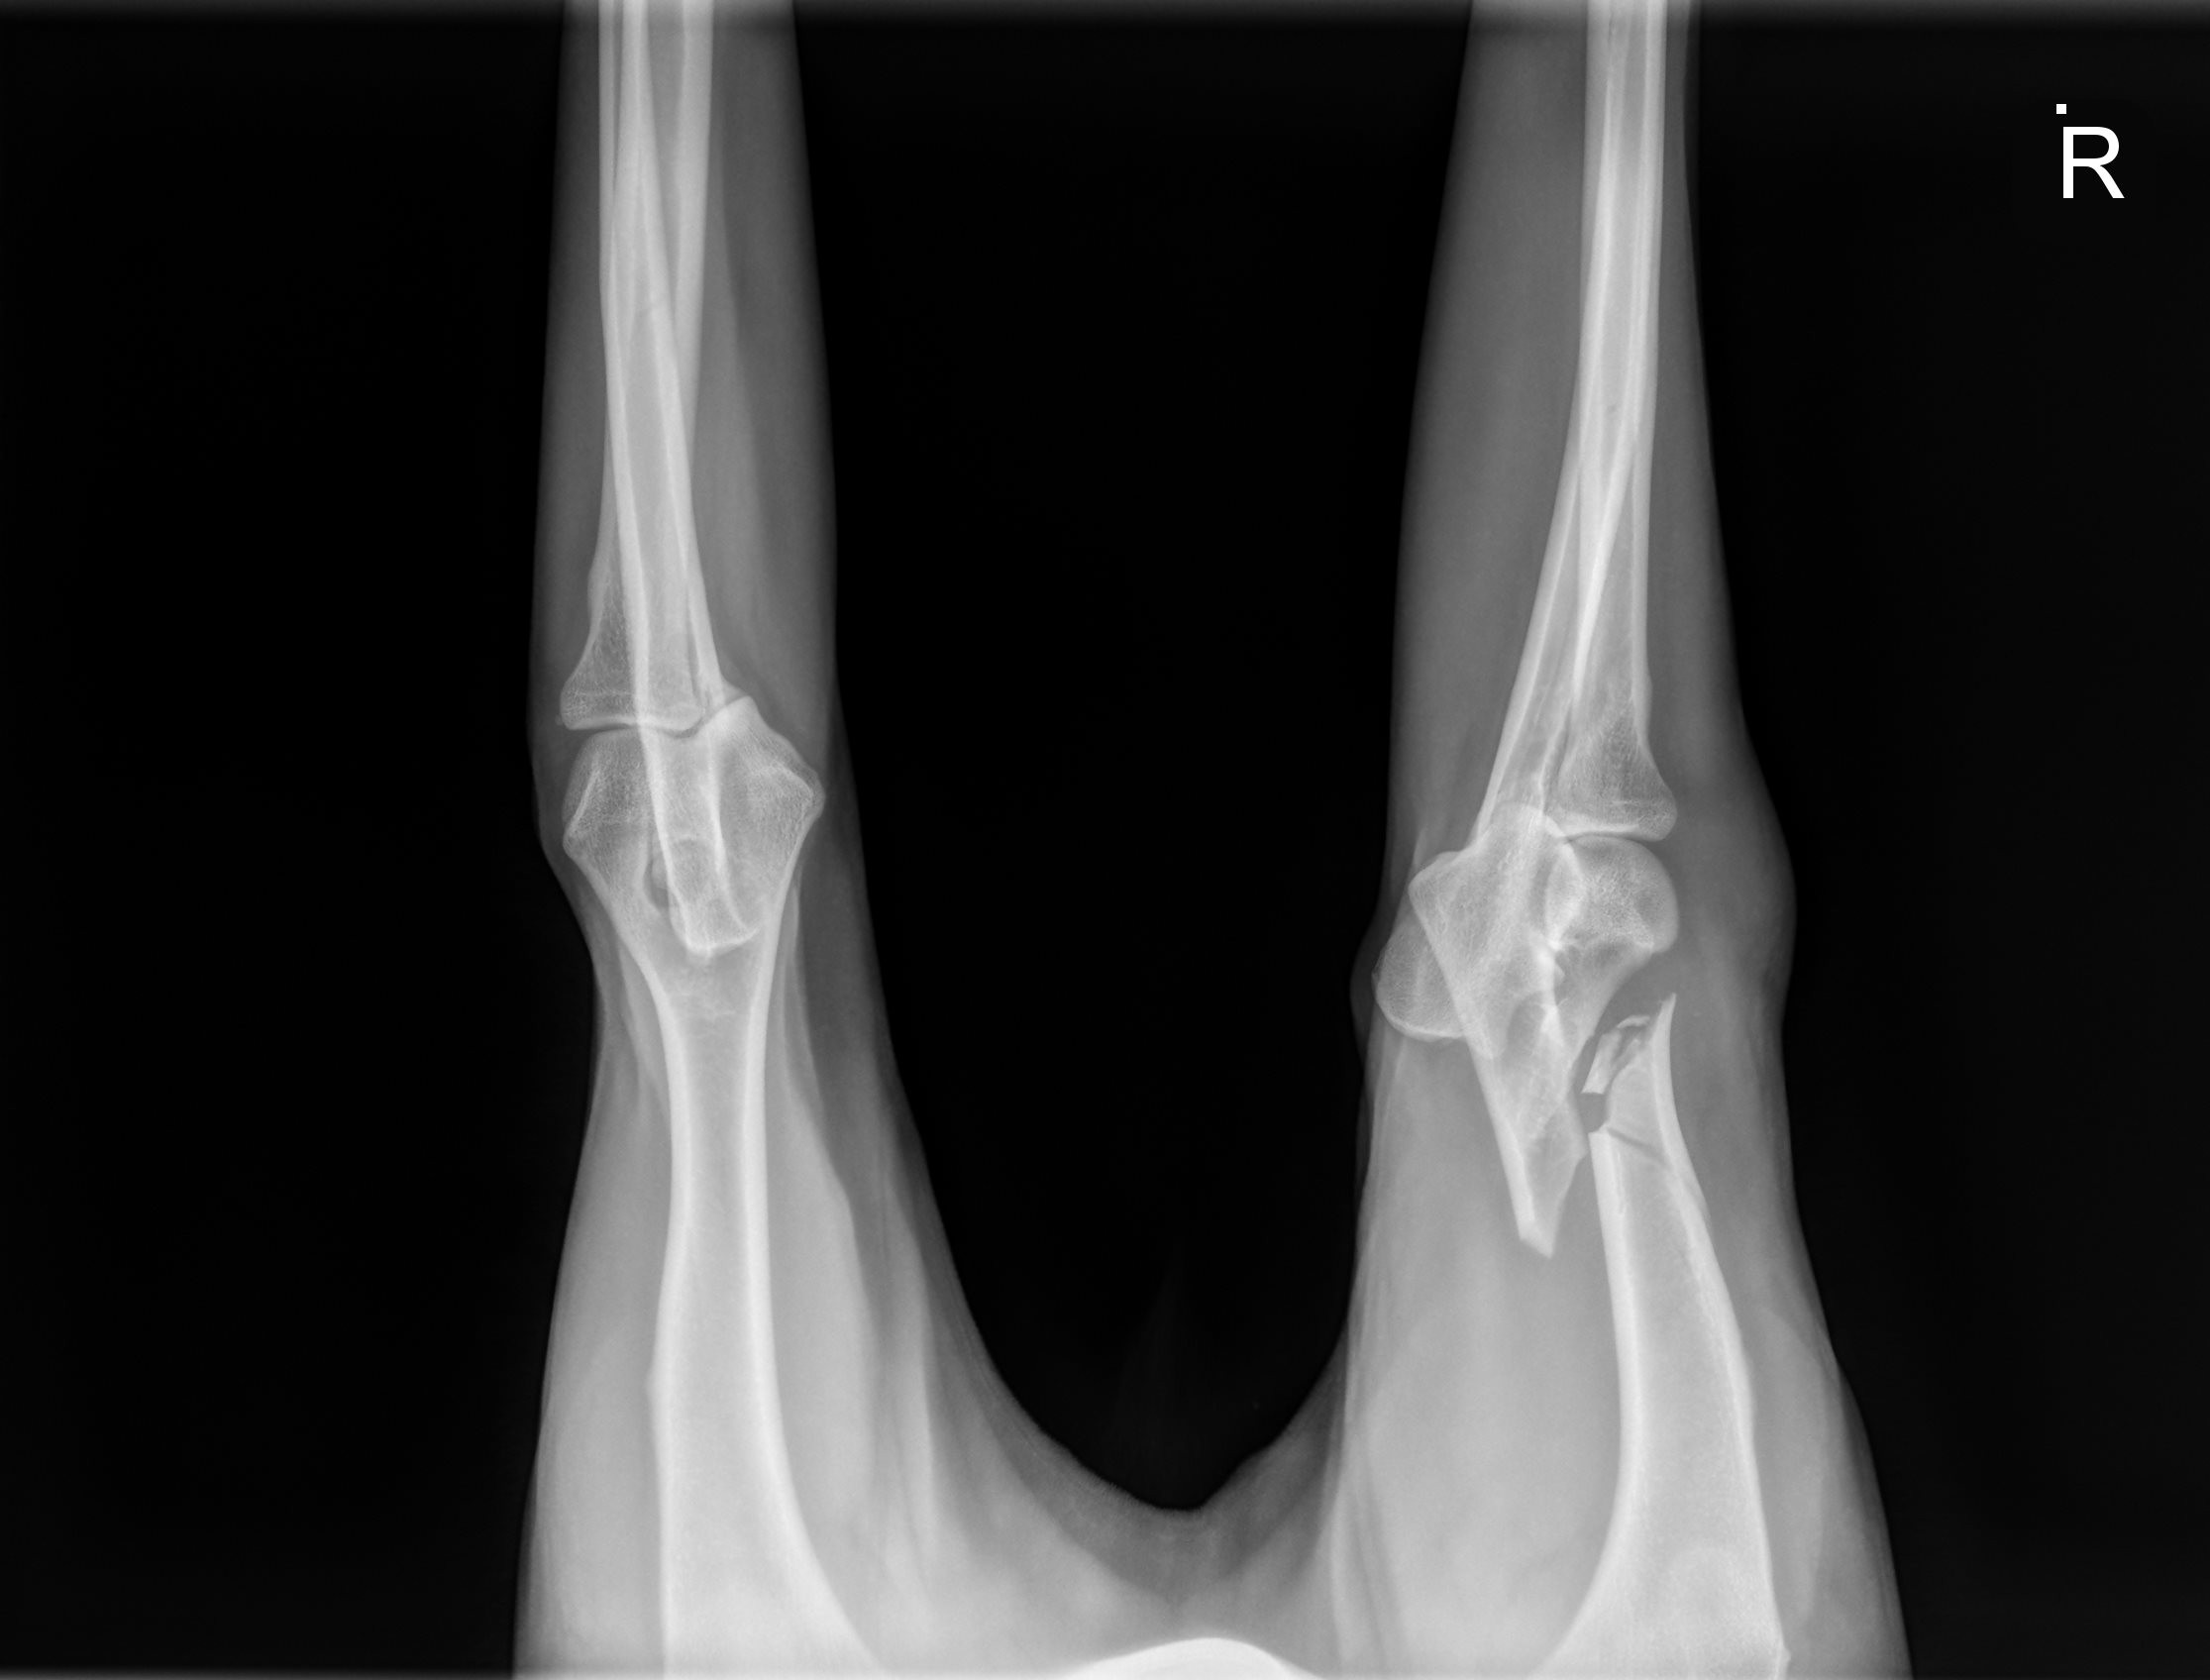

River is a sweet, gentle 1 1/2 year old golden, who had a tragic fall down a flight of stairs and fractured his humerus bone. Due to financial hardship and the physical challenges of navigating multiple flights of stairs, River’s family made the heartbreaking decision to surrender him to GRR so he could receive the care he desperately needed.

This type of injury is incredibly painful and requires specialized surgery to repair. Without it, River’s chances of ever walking, playing, or living a pain-free life are at risk. Watching him struggle to stand and looking into his eyes as he winces in pain is heartbreaking.

On Tuesday (10/30/2025) afternoon, his leg was surgically repaired using plates, screws & pins.  We are hoping his will be fully recovered in 8 weeks.